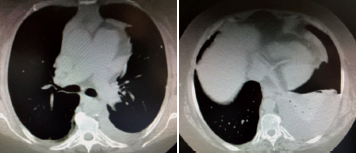

Donna di 72 anni, casalinga e non fumatrice. Anamnesi patologica: ipertensione arteriosa sistemica ed insufficienza renale da 15 anni; da 5 anni fibrillazione atriale permanente in trattamento con anticoagulanti orali. Due mesi prima del ricovero l’ecografia cardiaca rilevava dilatazione atriale sinistra, volume ventricolare sinistro lievemente aumentato e normale funzione sistolica globale senza alterazioni della cinesi zonale. Da un mese comparsa di dispnea da sforzo che diventava ingravescente per cui si rivolgeva al Pronto Soccorso dove una radiografia del torace mostrava un versamento pleurico sinistro (Figura 1). Gli esami in PS: BNP 395 pg/mL, azotemia 61 mg/dL, creatinina 2,05 mg/dL, Hb 11,9 g/Dl, Ht 36,7%; ECG: F.A. normofrequente (77 bpm) IVSx con scarsa progressione della R da V1 a V4 e anomalie aspecifiche della ripolarizzazione. Il collega Cardiologo ritieneva che il versamento pleurico non fosse cardiogeno per cui la paziente veniva ricoverata in Pneumologia. Il giorno successivo posizionavamo, dopo ecografia toracica, drenaggio pleurico 12 fr con estrazione di LP 1500 cc giallo-arancio (essudato). Si proponeva alla paziente toracoscopia diagnostica, data la valutazione cardiologica e il BNP inferiore a 500 pg/mL 1, e si eseguiva TC torace (Figura 2) che confermava il versamento pleurico sinistro con atelettasia compressiva del LIS senza altre lesioni polmonari e pleuriche e senza adenopatie mediastiniche.

Figura 2.TC torace: versamento pleurico sinistro con atelettasia del LIS.